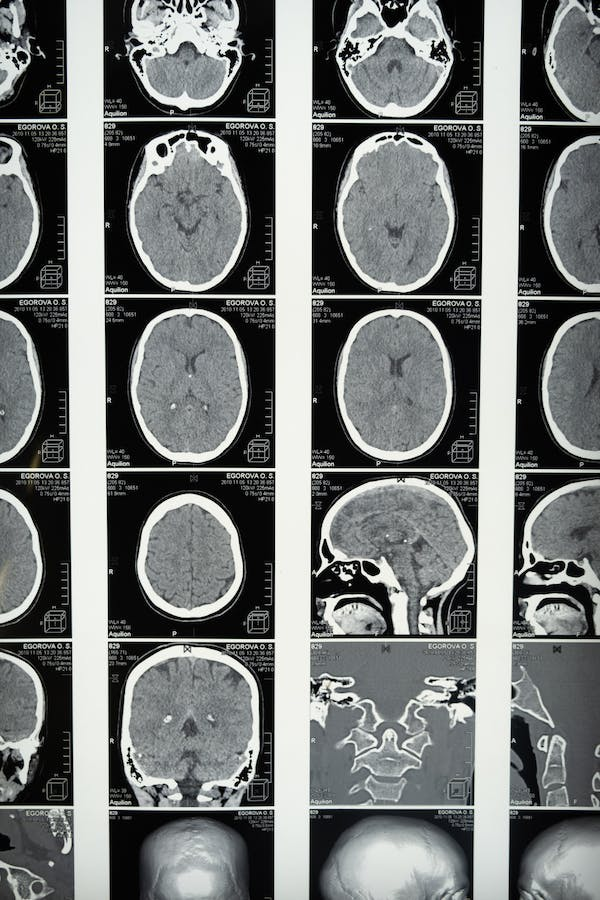

Si bien los síntomas característicos pueden ser suficientes para obtener un diagnóstico, también pueden identificarse otros signos que coinciden con esta afección. Así, desviaciones de las estructuras mediales cerebrales, herniación, hundimiento del cuero cabelludo y profundización de los surcos cerebrales suelen estar asociados a la patología. En este sentido, suelen utilizarse técnicas de radiografía como la tomografía computada (computed tomography, CT, en inglés) y resonancia magnética (magnetic resonance imaging, MRI, en inglés) para evaluar dichos aspectos.